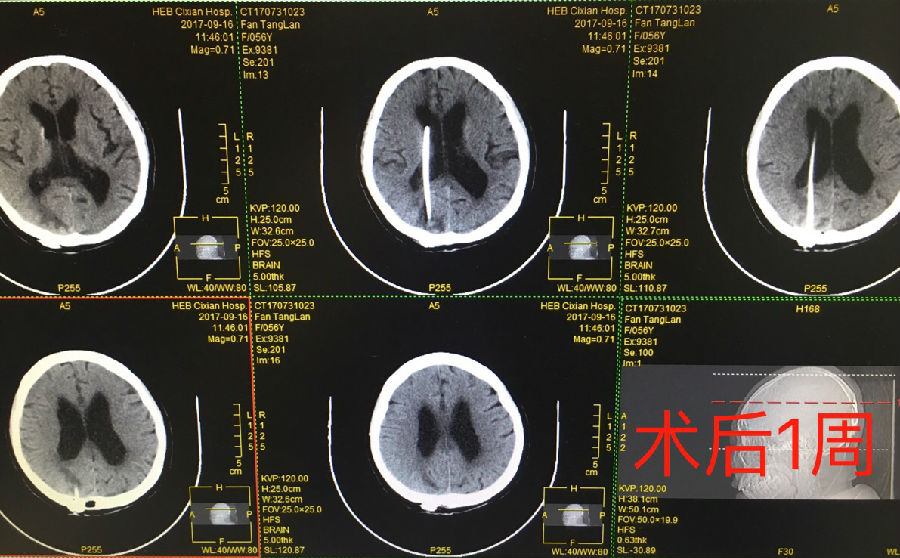

該科同時(shí)完成了首例腦積水患者利用Flushing 儲(chǔ)液囊uniGAV 分流技術(shù)行腦室腹腔分流術(shù),手術(shù)取得了良好的效果,在我院腦積水的治療上具有開(kāi)創(chuàng)性的意義。